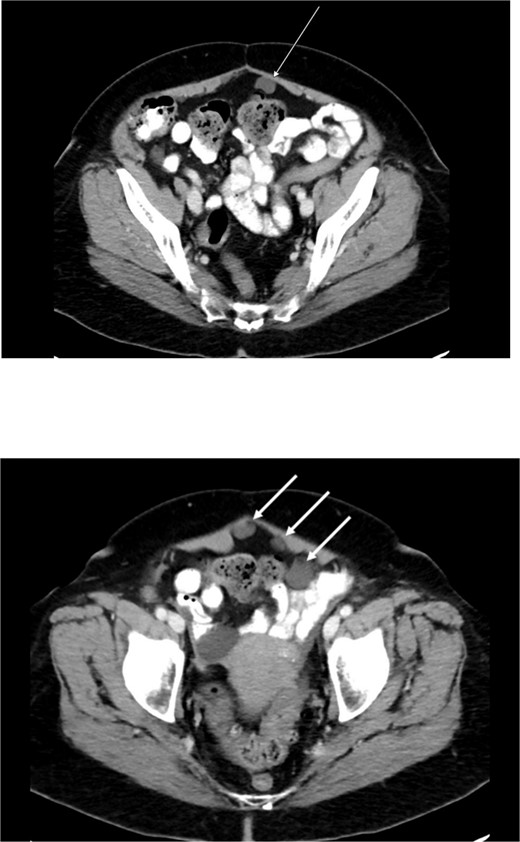

Preoperative abdominal computed tomography revealed a mass in the ascending colon (Fig. 1) and multiple nonspecific cystic lesions in the peritoneal cavity involving the abdomen and pelvis (Fig. 2). Normally, carcinomatosis would be suspected in a patient with mucinous adenocarcinoma of the colon. However, the radiographic findings were not definitive for carcinomatosis, and the history of abdominal ‘cysts’ 20 years previously further confused the situation. The differential at the time included malignant carcinomatosis, benign endometriotic cysts, and cystic peritoneal reaction to previously placed intraperitoneal hernia mesh. Carcinoembryonic antigen measured 0.8 ng/mL.

Computed tomography abdomen/pelvis—arrow indicates ascending colon mass.